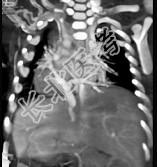

- 多项选择题女性,21岁, 活动后呼吸困难,时常发生上呼吸道感染, CT扫描如图所示,请选择正确的选项 ( )

A、考虑为肺静脉异位引流

D、该病人肺静脉异位引流入下腔静脉

E、该病人为心下型肺静脉异位引流